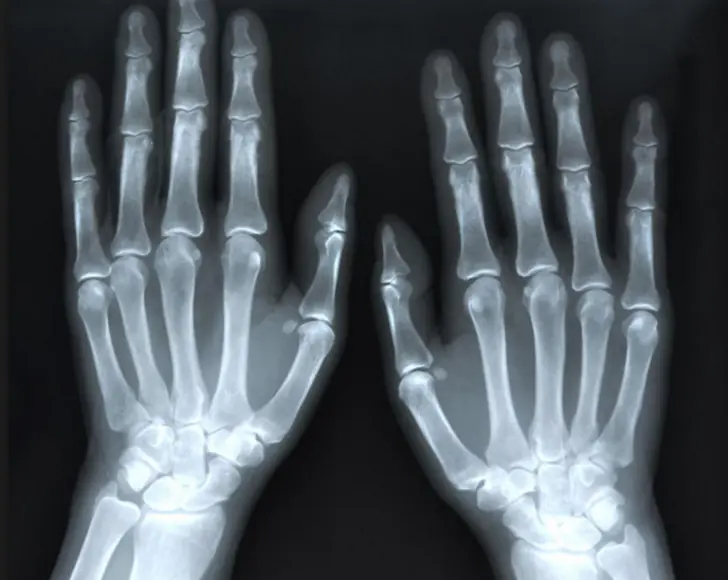

Muchas personas piensan que el sonido que escuchamos al crujir los nudillos verdaderamente es producido por algún tipo de fricción entre los huesos.

Pues aquí vienen las buenas noticias. No tiene nada que ver con los huesos.

En cada una de las articulaciones existe algo llamado líquido sinovial, un fluido con la consistencia de la clara de huevo.

Este líquido actúa como lubricante entre los huesos para facilitar su movimiento y juega un papel clave en el chasquido que se escucha cuando crujes los nudillos.

A pesar de que suena como un ruido producido por el roce de algo sólido, en realidad proviene de algo líquido.

Se solía pensar que el sonido era producido al hacer estallar las burbujas de gas que integraban el líquido sinovial, pero el año pasado gracias a un video de rayos X se pudo demostrar que el sonido de la explosión proviene en realidad de un vacío que se forma de repente en el líquido sinovial.

Es decir, el sonido se produce al separar los huesos produciendo así una cavidad hueca de forma repentina en el espacio que ocupa el líquido sinovial.